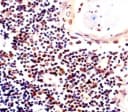

IgG1Applications: